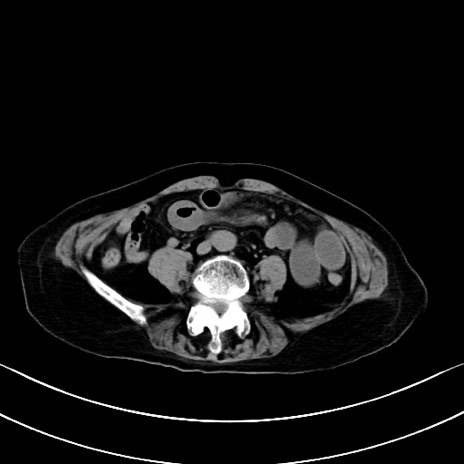

横断像

他院CT